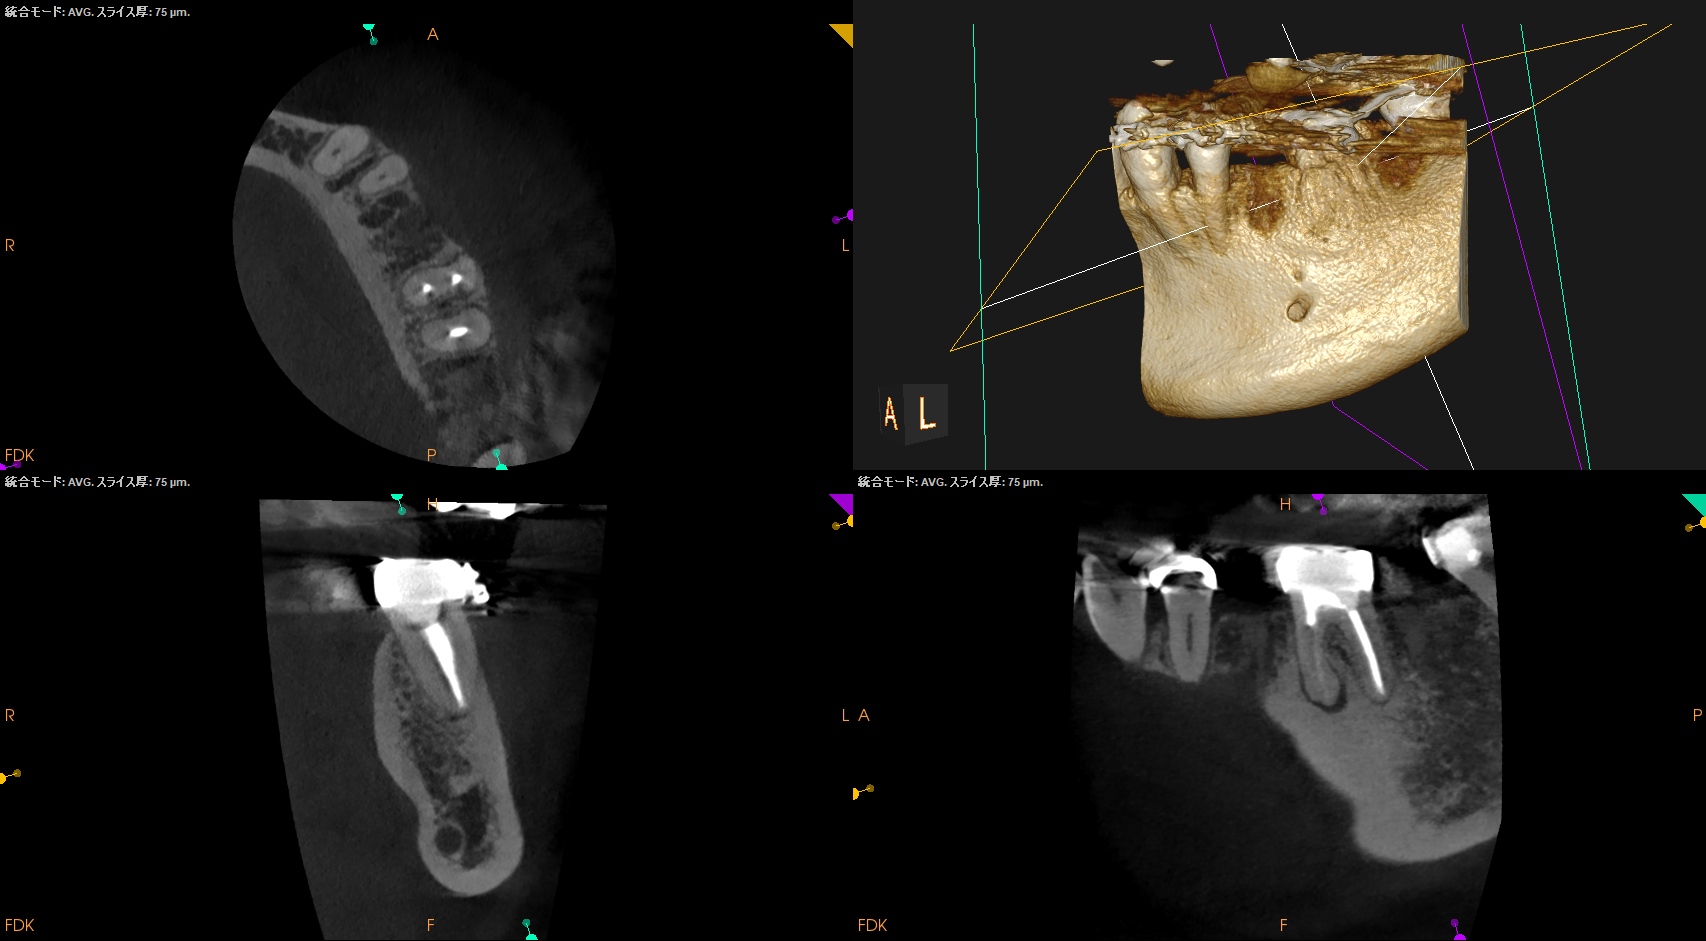

術後にPA, CBCTを撮影した。

#19 MB

#19 ML

#19 D

問題はないと思われる。